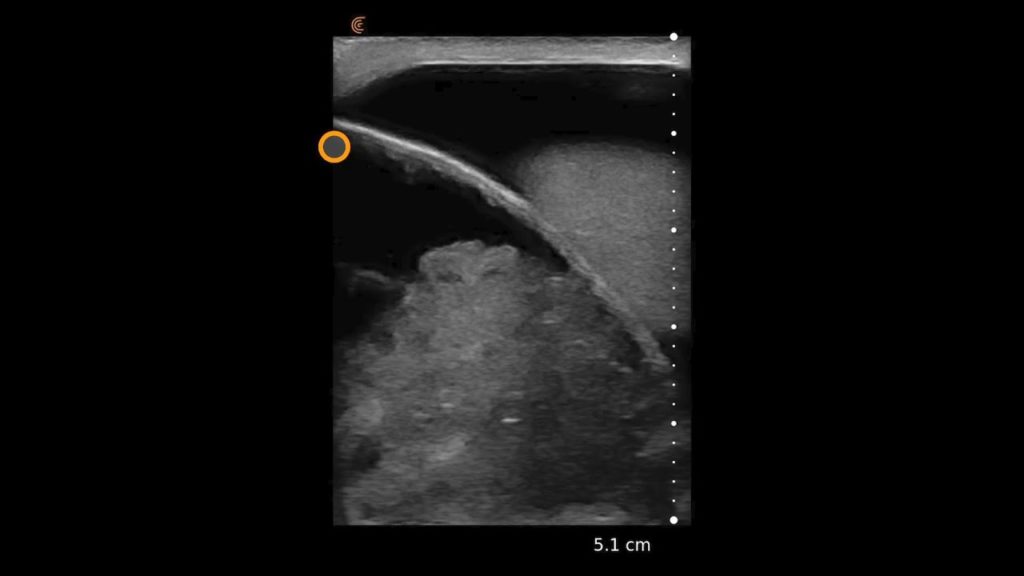

An overview scan of the shoulder can identify some of the most common pathologies that cause acute and chronic shoulder pain such as rotator cuff tendinopathy and tears, joint effusion, and bursitis.